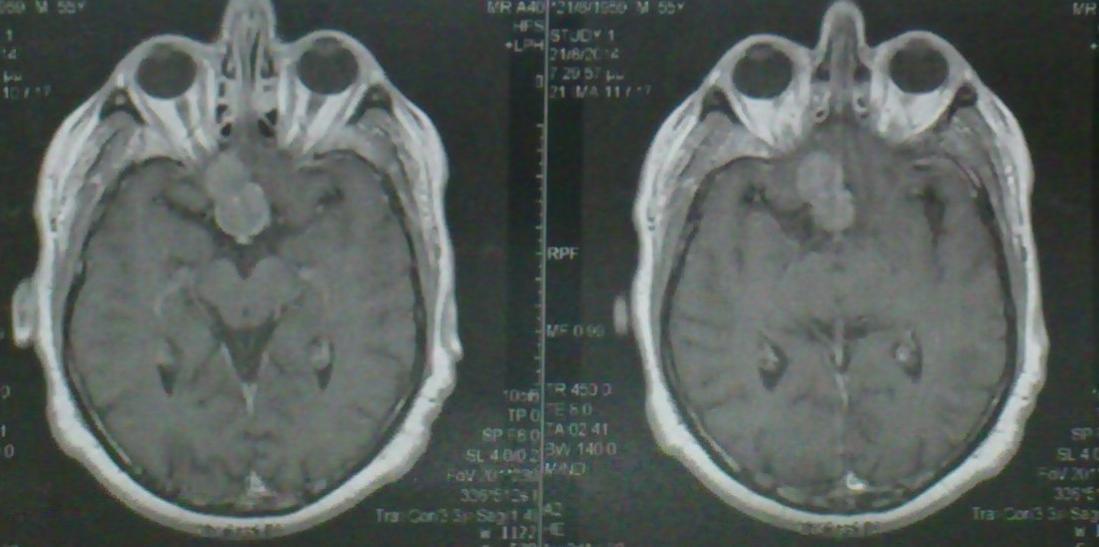

Ασθενής   55 ετών  ο οποίος είχε υποβληθεί  προ 3μήνου σε ενδοσκοπική διασφηνοειδική αφαίρεση μακροαδενώματος υπόφυσης  ( αδύνατη λόγω σκληρής σύστασης του όγκου η αφαίρεση του υπερεφιππιακού τμήματος του όγκου) προσήλθε στην κλινική μας  με σκοπό την αφαίρεση  του υπερεφιππιακού τμήματος του όγκου  δια υπερόφρυας τομής δέρματος και δεξιάς mini orbitozygomatic keyhole approach.  Η μετεγχειρητική του πορεία ήταν ομαλή με περαιτέρω βελτίωση των οπτικών του πεδίων ( αρχική μικρή  βελτίωση μετά την ενδοσκοπική διασφηνοειδική προσπέλαση ) και ο απεικονιστικός έλεγχος ανέδειξε την πλήρη αφαίρεση του υπολειμματικού όγκου.

Προεγχειρητικός απεικονιστικός έλεγχος